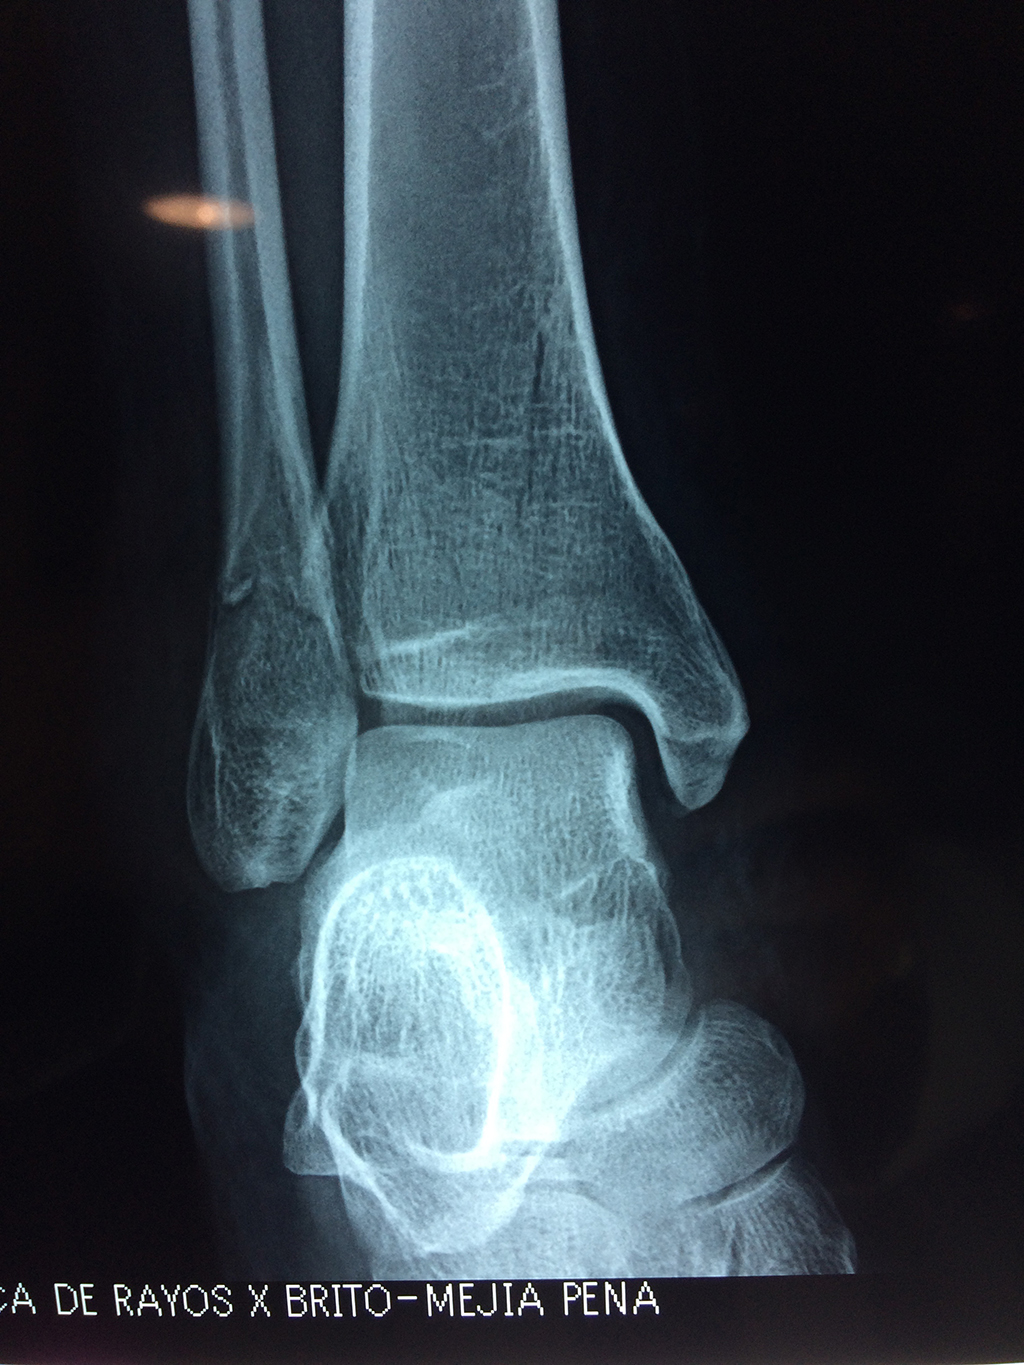

Una fractura de tobillo es la rotura de uno o más de los huesos del tobillo. Estas fracturas pueden ser:

- Parciales (el hueso está sólo parcialmente fisurado, no del todo).

- Completas (el hueso está perforado y está en 2 partes).

- Producirse en uno o ambos lados del tobillo.